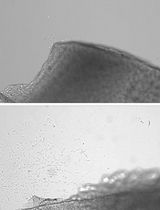

- Cultivation on a fibrin carrier- Seed hair follicle stem cells derived from a dual reporter mouse at 1 x 105 cells/ml onto a fibrin carrier and cultivate for 3 days in stem cell media (Recipe 3) at 37 °C, 5% CO2. A total volume of 2 ml is used for each well. Cells can be visualized using phase contrast microscopy (Figure 1)

Figure 1. Scheme showing transplant of a fibrin carrier containing bulge derived hair follicle stem cells. Discs are prepared from hair follicle stem cells (HFSCs) from a dual reporter mouse cultivated for 3 days on a fibrin sheet by using the back of a pipet tip as a “cookie cutter”. Discs are then sutured to the eye of a limbal stem cell deficient mouse. Four sutures (red asterisks) are placed. Cells fluoresce red but not green as they do not yet express the corneal epithelial differentiation marker, Krt12.